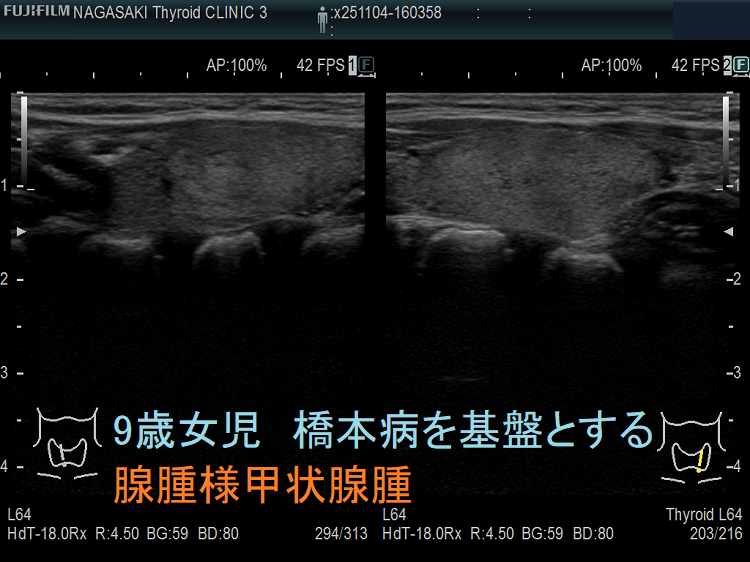

成人と同じく、小児にも橋本病を基盤とする腺腫様甲状腺腫が存在します。最も、橋本病の罹病期間は、大人と比べて遥かに短いため、腺腫様甲状腺腫にまで発展するケースは少ない。下記は、成長障害から甲状腺機能低下症と、橋本病を基盤とする腺腫様甲状腺腫が見つかった9歳女児のケースです。